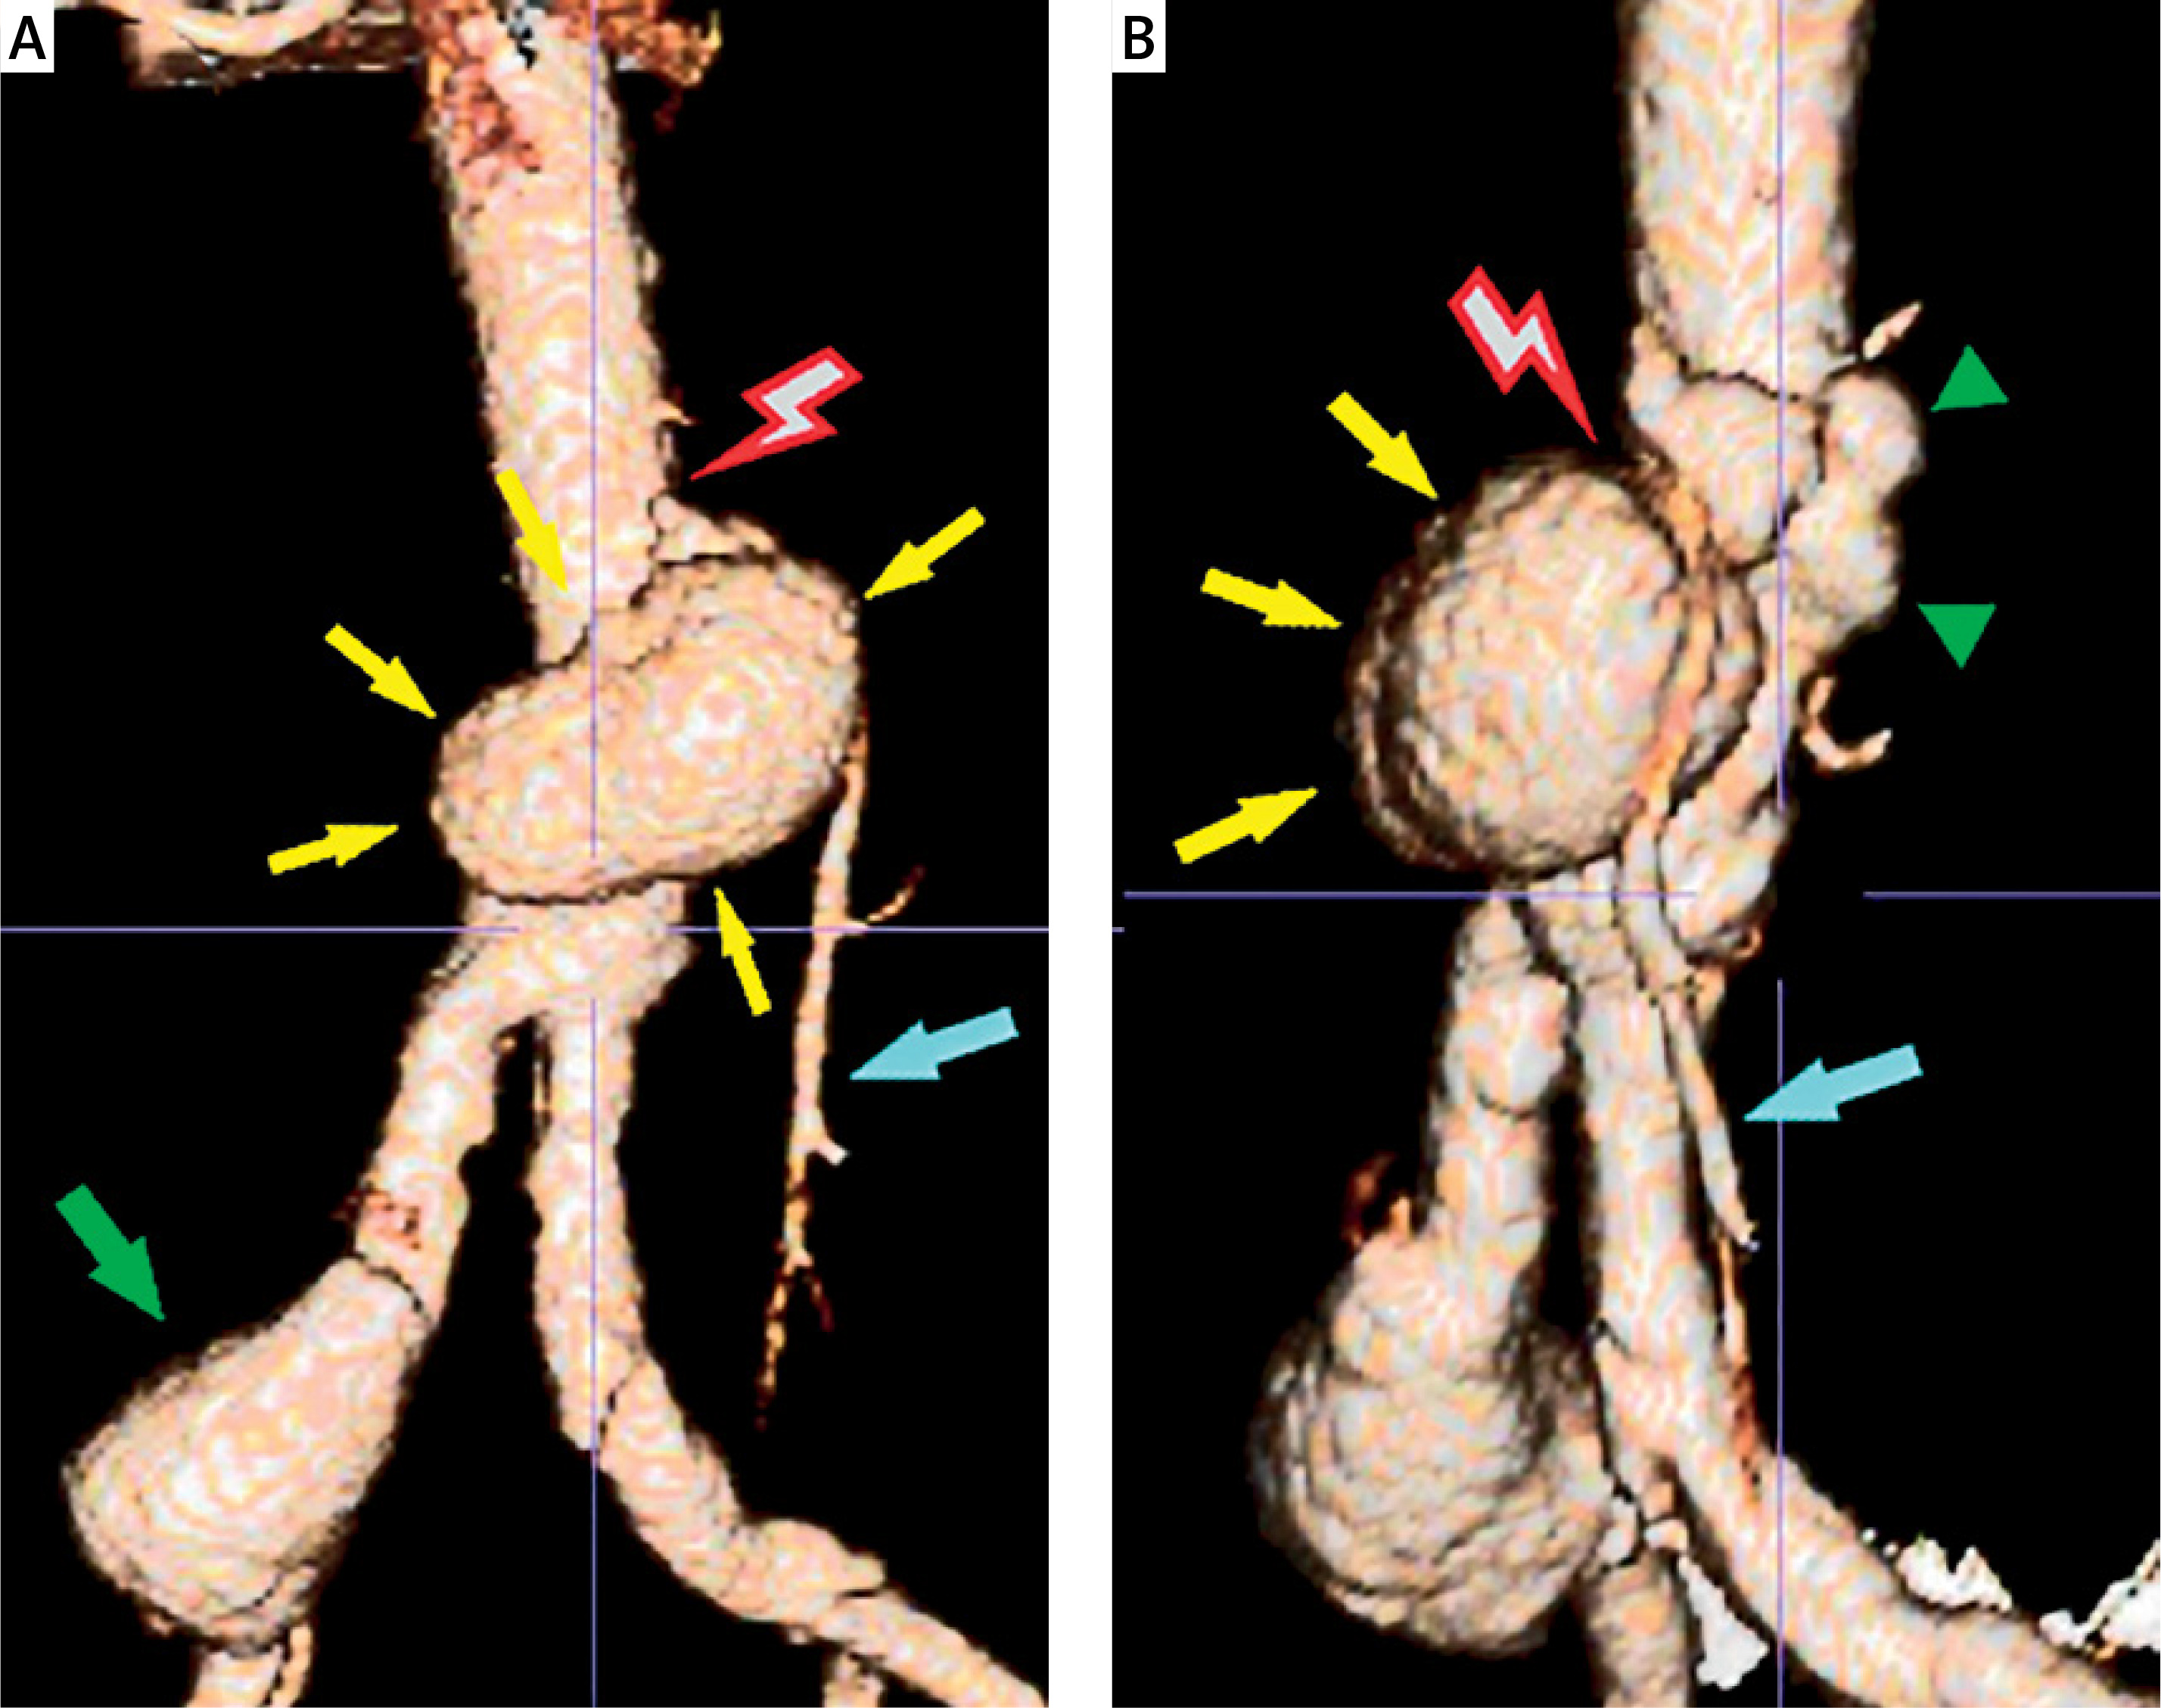

Figure 4

Computed tomography angiography (CTA), 3D-reconstruction (A – coronal view: red lightning bolt: aortic rupture due to avulsion of the inferior mesenteric artery, yellow arrows: aortic pseudoaneurysm, green arrow: right common iliac artery aneurysm, light blue arrow: inferior mesenteric artery), (B – oblique view: red lightning bolt: aortic rupture due to avulsion of the inferior mesenteric artery, yellow arrows: aortic pseudoaneurysm, green arrowheads: focal aortic dilatation, light blue arrow: inferior mesenteric artery)